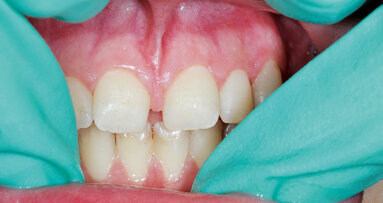

Klinický případ, kterým dále uvádím, je skvělým příkladem toho, jak obtížné je určit původ pacientových symptomů pouze na základě intraorálního snímku. Vizualizace 2D snímku selhává v jistotě určení přítomnosti léze, ještě důležitější však je, že je nemožné určit velikost, morfologii a typ léze, kterou se podaří nalézt. Analýza 3D snímku nám poskytne jasnou představu o klinické situaci: koronální a sagitální řezy odhalily přítomnost veliké léze sahající od apexu meziálního kořene tohoto moláru do furkace, zatímco axiální řezy nám umožňují provést přesnou analýzu endodontické anatomie a obzvláště pak tvaru meziálního kořene, který byl v tomto případě spojen s palatinálním kořenem. Celkový přehled o situaci ovlivňuje rozhodování o postupu a stanovení léčebného plánu zahrnujícího speciální úkony (obr. 1–4).